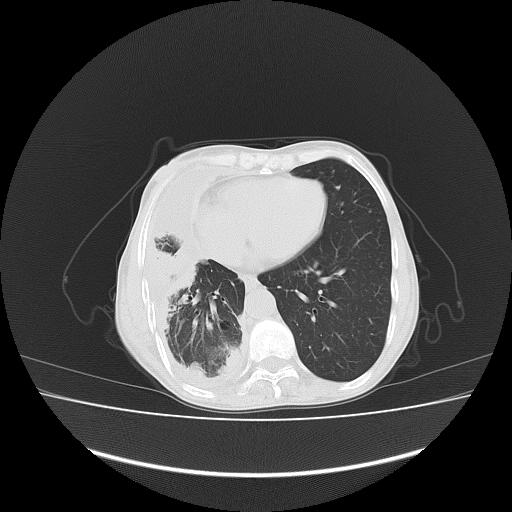

标题: CT16930:女 59 胸痛6个月 胸水脱落细胞学见瘤细胞 [打印本页]

标题: CT16930:女 59 胸痛6个月 胸水脱落细胞学见瘤细胞

可见多发肺内病灶,且胸膜病灶较多有圆球状而非丘状,多考虑胸膜转移瘤伴胸腔积液,右侧胸廓缩小固定,且部分病灶呈丘状,尚不除外恶性胸膜间皮瘤伴肺内转移

右侧胸膜增厚,局部呈结节状增厚,右侧胸腔少量积液。双肺未见确切肿块影。纵隔未见淋巴结肿大。气管、支气管通畅。考虑右侧胸膜间皮瘤(恶性?)可能性大。不除外癌性胸膜炎。

恶性胸膜间皮瘤伴肺内转移可能性大;或胸膜、肺内均为转移瘤,左肺下叶亦见多发小结节影。

右侧胸廓塌陷,右侧胸膜广泛增厚并见多发胸膜结节,右侧少量胸腔积液并包裹。

右侧广泛胸膜增厚,局部呈结节状增厚,右侧胸腔少量积液。双肺未见确切肿块影。纵隔未见淋巴结肿大。气管、支气管通畅。考虑右侧胸膜间皮瘤(恶性?)可能性大。支持!

胸膜转移瘤  包裹性胸腔积液  肺内转移

右胸腔结节均考虑来自胸膜(部分来源于叶裂),考虑胸膜间皮瘤或转移瘤.